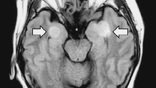

От 5 до 10 процентов коронавирусных больных в госпиталях демонстрируют проблемы с мозгом и центральной нервной системой в целом (например, они могут кратковременно терять сознание). Однако, как считают специалисты, на самом деле таких пострадавших может быть больше, так как многие люди находятся под наркозом или же подключены к аппаратам ИВЛ.

Согласно одному из мнений, ствол головного мозга из-за вторжения вируса перестаёт ощущать нехватку кислорода (поэтому пациенты не задыхаются, даже если уровень кислорода в крови очень мал). В норме именно эта часть мозга отвечает за этот врождённый рефлекс.

Как вирус попадает в мозг – большой вопрос. Один из возможных путей: через нос и обонятельные луковицы. Однако учёным ещё предстоит разобраться, так ли это на самом деле или есть другие "обходные пути".